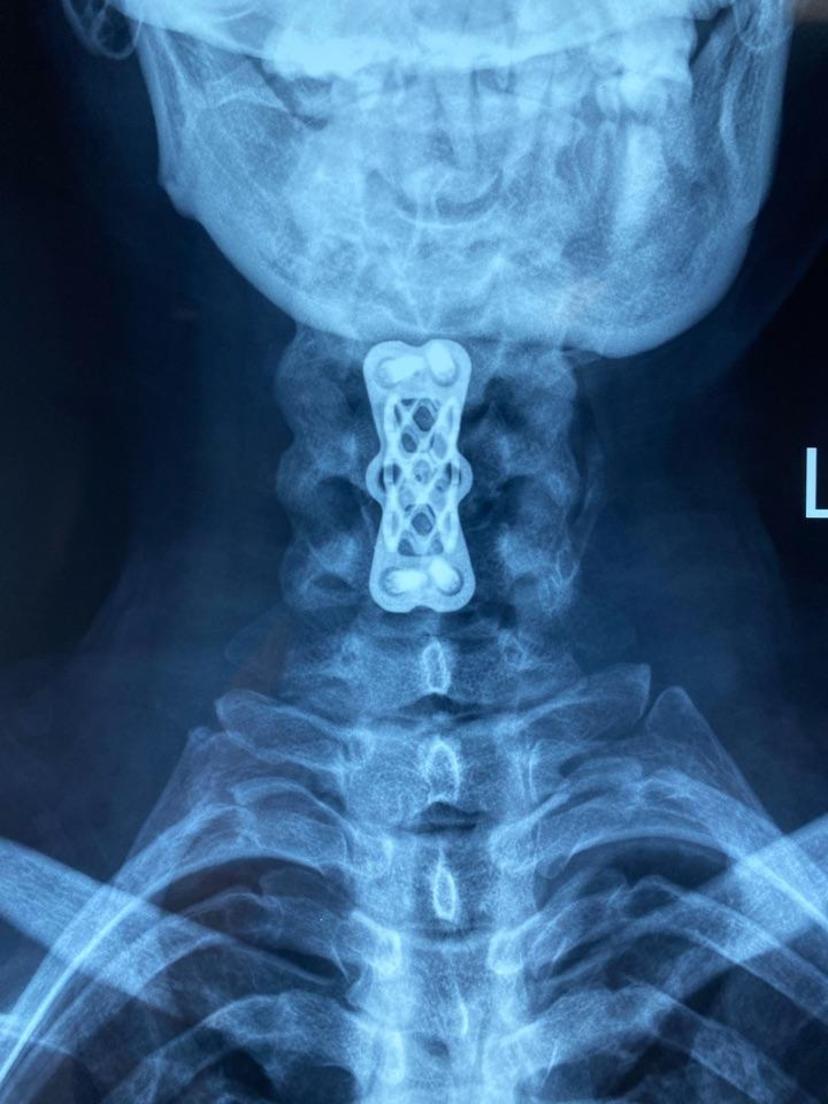

患者颈痛10年,诊断颈椎病,曾多次给予针灸、小针刀、口服药物等治疗,效果不明显,手麻及行走不稳逐渐加重,经CT及磁共振检查后,诊断两节段椎间盘突出合并严重后纵韧带骨化,经前路ACCF微创手术,完全去除了压迫神经脊髓的物体,术后当晚明显感到四肢力量增大,麻木感好转,第二天自行下地行走,第三天康复出院!两节段颈椎间盘突出

CT显示减压充分,致压物完全去除,生理曲度恢复

位置良好